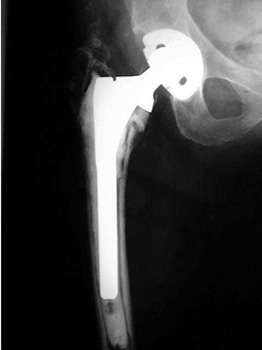

LooseningAs pain and disability due to loosening become severe enough to require revision arthroplasty, abnormalities in the binding of the cement to the bone or prosthesis are almost always visible radiographically. Radiographic abnormalities include:

No prior studies available. Abnormally widened interfaces about femoral component at Gruen zones 1, 6, and 7. Osteolysis at Gruen zone 5 with marked thinning of femoral cortex placing patient at risk for pathologic fracture.